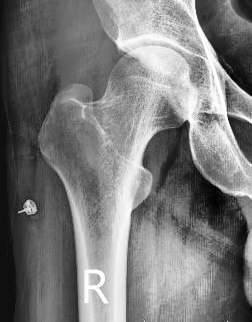

r_result_7สมชาย.jpg                      16-Apr-2024 04:27               34704